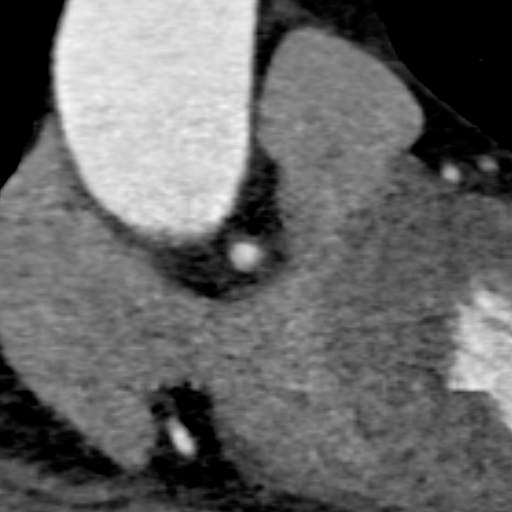

主动脉CT

主动脉瓣环平均直径:22.4mm

左室流出道平均直径:23.2

左冠脉开口:10mm

右冠脉开口高度:14.7mm

患者为功能性二叶瓣,左右瓣叶融合,左冠脉开口低,窦部大,冠脉风险低。

袁义强院长总结了该病例特点:功能性二叶瓣主动脉瓣狭窄,患者有心衰症状,解剖适合TAVR,年龄66岁,存在明确TAVR手术适应症。选择右股动脉入路,根据CT测量分析选择瓣膜大小,窦部情况可,瓣环平均直径22.4mm,选择植入24mm瓣膜。